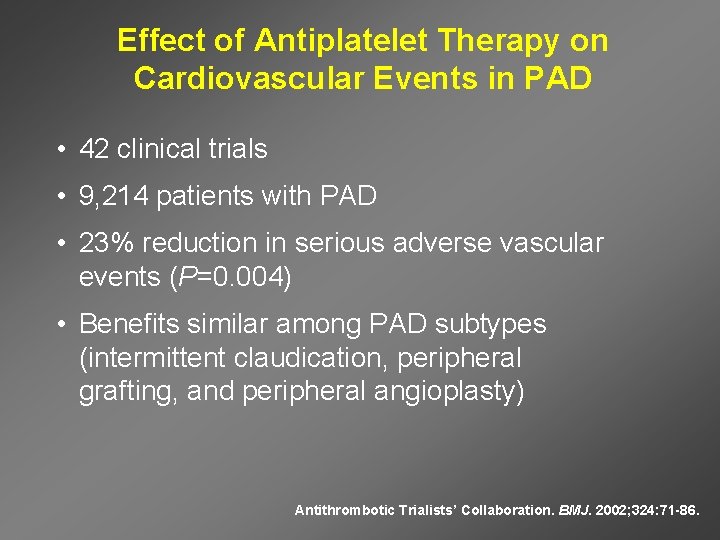

Effect of Antiplatelet Therapy on Cardiovascular Events in PAD • 42 clinical trials • 9, 214 patients with PAD • 23% reduction in serious adverse vascular events (P=0. 004) • Benefits similar among PAD subtypes (intermittent claudication, peripheral grafting, and peripheral angioplasty) Antithrombotic Trialists’ Collaboration. BMJ. 2002; 324: 71 -86.